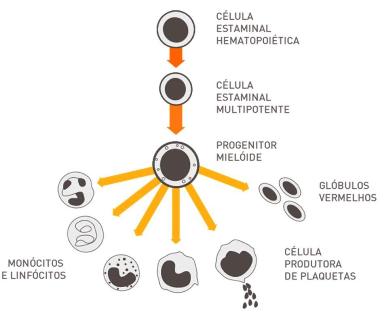

Células estaminais hematopoiéticas – As células estaminais adultas melhor caracterizadas são as células estaminais hematopoiéticas (EH), que originam todas as células sanguíneas tais como os eritrócitos, linfócitos e plaquetas (Figura 2). As células EH estão sobretudo localizadas na medula óssea, no sangue periférico, mas também em alguns órgãos (por exemplo: baço e fígado), e ainda no sangue do cordão umbilical e na placenta. As células EH são caracterizadas pela expressão de marcadores de superfície celulares específicos, importantes no isolamento destas células.

Figura 2 – Diferenciação das células estaminais hematopoiéticas.